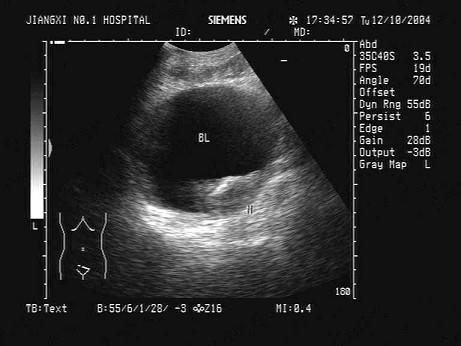

问题 某患者因血尿就诊,下腹部声像图如图,根据图中表现及所标志的体位,最可能的超声诊断为?(?)

选项 A.前列腺增生并钙化 B.膀胱结石 C.膀胱癌 D.前列腺癌 E.膀胱血块

答案 C